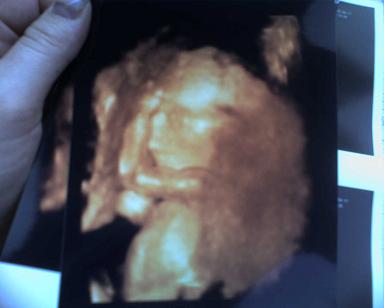

Niki, igen, holnap megyünk, mar nagyon izgulok :D

az uj ultrahang kep felkerül ide, persze :D

remelem lesz kedve mininek ´modellkedni´jo lenne sokat latni belöle :D

csüt.ön nem dolgozom, de megprobalom mar otthon felrakni a kepet, bar azt hiszem laci sem dolgozik, es lehet, hogy kirandulni fogunk..ja..engem most vervetelre fognak küldeni, ugye? afp..na majd meglatom, de ahogy lesz idöm, megmutatom nektek :D

jo lenne megtudni a nemet, de sztem nem fogja megmutatni, bar mi meg mindig kislanyt erzünk :D